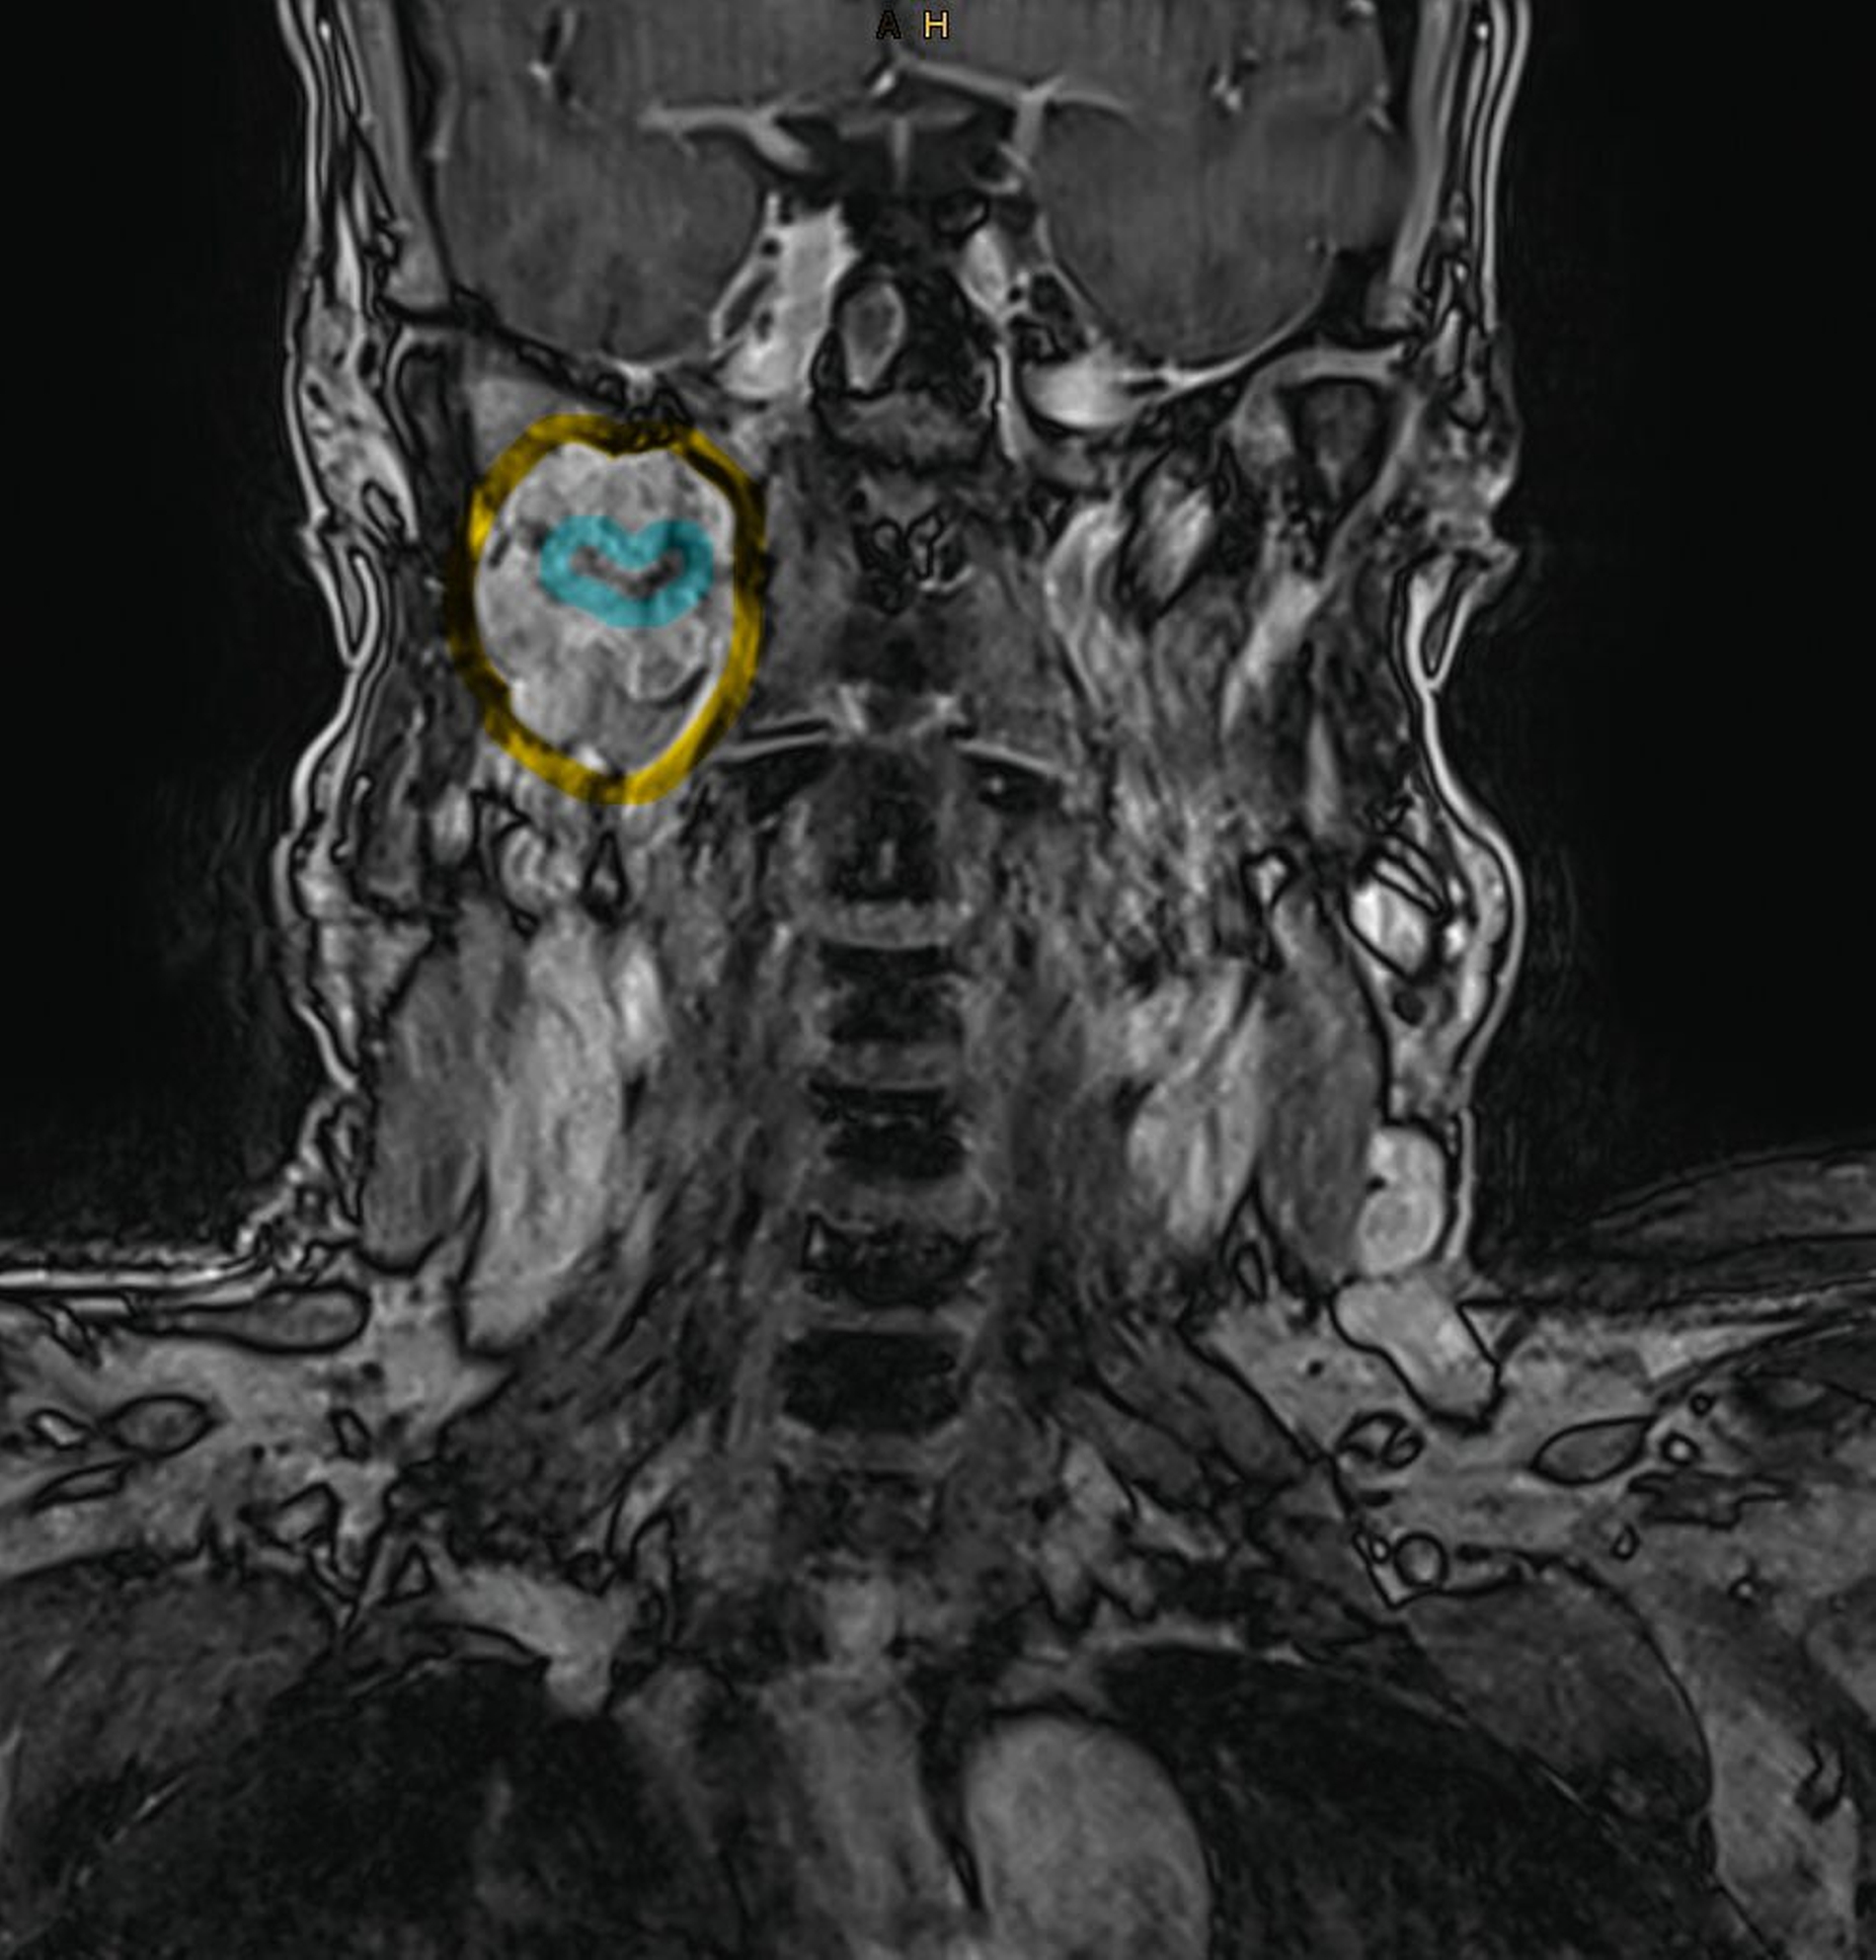

In der extern durchgeführten MRT der Halswirbelsäule vom 18. Dezember 2025 zeigte sich randständig eine angeschnittene Raumforderung im rechten Parapharyngeal- und Mastikatorraum, so dass eine gezielte weiterführende Bildgebung veranlasst wurde. Die kontrastmittelgestützte MRT vom 30. Dezember 2025 ergab eine inhomogene, gut abgrenzbare Raumforderung im rechten Parapharyngeal- und Mastikatorraum mit einer maximalen axialen Ausdehnung von 52 mm x 28 mm.

Ein vaskulärer Ursprung konnte mittels dynamischer Sequenzen ausgeschlossen werden. Die Raumforderung wuchs verdrängend bis an den Musculus pterygoideus heran und hatte einen langstreckigen Kontakt von > 90° zur A. carotis interna. Zusätzlich bestand eine schlitzförmige Kompression der V. jugularis interna sowie eine fokale Teilthrombosierung der V. facialis communis. Pathologisch vergrößerte Lymphknoten waren nicht nachweisbar.

Zur besseren räumlichen Einschätzung wurde das MRT-Datenset mittels der Open-Source-Software 3D Slicer segmentiert [Fedorov et al., 2012]. Mithilfe der Funktion „Grow from seeds“ erfolgte eine separate Segmentierung des Unterkiefers und der Raumforderung, ergänzt durch manuelle Korrekturen.

Metallartefakte durch zahnärztliche Restaurationen im rechten Unterkiefer wurden berücksichtigt. Die dreidimensionale Rekonstruktion verdeutlichte die enge Beziehung des Tumors zur A. carotis interna und unterstützte die Indikationsstellung für einen erweiterten operativen Zugang.

Die präoperative 3D‑Segmentierung erwies sich als wertvolles Instrument zur räumlichen Orientierung und zur Operationsplanung. Sie verbessert das Verständnis komplexer anatomischer Verhältnisse, unterstützt die Wahl des Zugangs und kann damit zur Risikoreduktion beitragen [Fedorov et al., 2012].